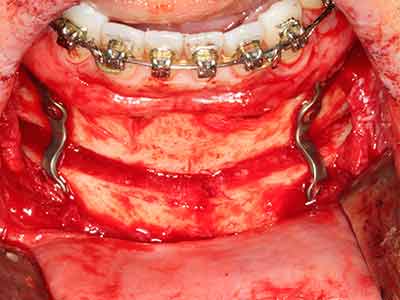

Aplicación: Partición ósea / Cortical Split

El tejido óseo no solo tiene un contenido puramente mineral, sino que también presenta una importante proporción de fibras de colágeno. Esto no solo garantiza una buena resistencia a la presión, sino también una cierta flexibilidad, que puede aprovecharse para la realización de aumentos. En la plastia de expansión clásica a efectos de una partición ósea, la cresta maxilar atrofiada se divide en su eje longitudinal y, tras alcanzar una profundidad de osteotomía suficiente, se extiende con cuidado (fig. 13-16), en un caso ideal sin desperiostizar de forma visible el maxilar (Brugnami, Caiazzo et al. 2014, Stricker, Fleiner et al. 2014). Los sistemas de tornillos y placas con distancia de expansión creciente han demostrado su eficacia para distanciar entre sí las dos tablas óseas por debajo del umbral de rotura. Por regla general, se requieren anchuras de hueso residual de al menos 3 a 4 mm (Chiapasco, Zaniboni et al. 2006) para garantizar una flexibilidad y una cobertura ósea suficientes de los implantes que van a incorporarse. En caso necesario, una osteotomía de descarga vertical unilateral o bilateral puede mejorar la flexibilidad. Como alternativa a la técnica clásica se ha descrito una combinación con otras técnicas de aumento, sobre todo en la parte bucal.

Con el uso de sierras piezoeléctricas la división se efectúa de forma especialmente cuidadosa y sin pérdidas importantes de las dimensiones, por lo que no se han encontrado diferencias significativas entre los implantes realizados en el maxilar dividido y en la cresta alveolar no deficitaria (Chiapasco, Zaniboni et al. 2006, Danza, Guidi et al. 2009). No obstante, precisamente en la partición profunda y limitada de forma local, es preciso asegurarse de que exista una adecuada irrigación por agua para evitar que se produzcan sobrecargas térmicas en las áreas de osteotomía apical.

Fig. 13: En este paciente de 52 años con una anchura del hueso residual del maxilar inferior de 4 mm, hay que asegurarse de que exista refrigeración por agua adecuada durante la partición del hueso.